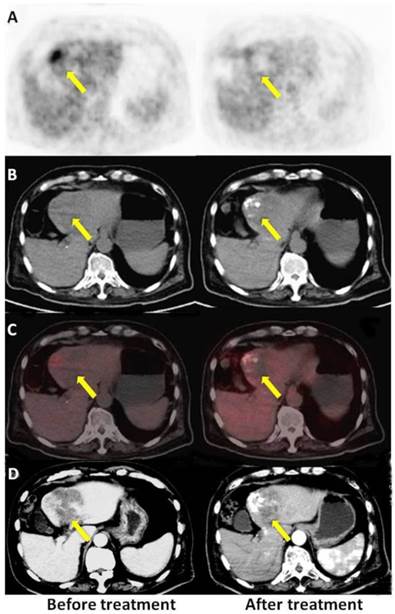

Figure 4

A: PET, B: CT, C: PET/CT fused axial images, and D: enhanced CT. A 70-year-old male with HCC (once TACE, OS 9.77 m, mRECIST PR, PET no response). The time elapsed after TACE was 30 d for enhanced CT and 34 d for the PET/CT scan, respectively. There was high tumor uptake in the first PET scan (left) and relatively low uptake in the second scan (right) after therapy, but the patient belonged to the PET non-response group, indicating a poor prognosis.